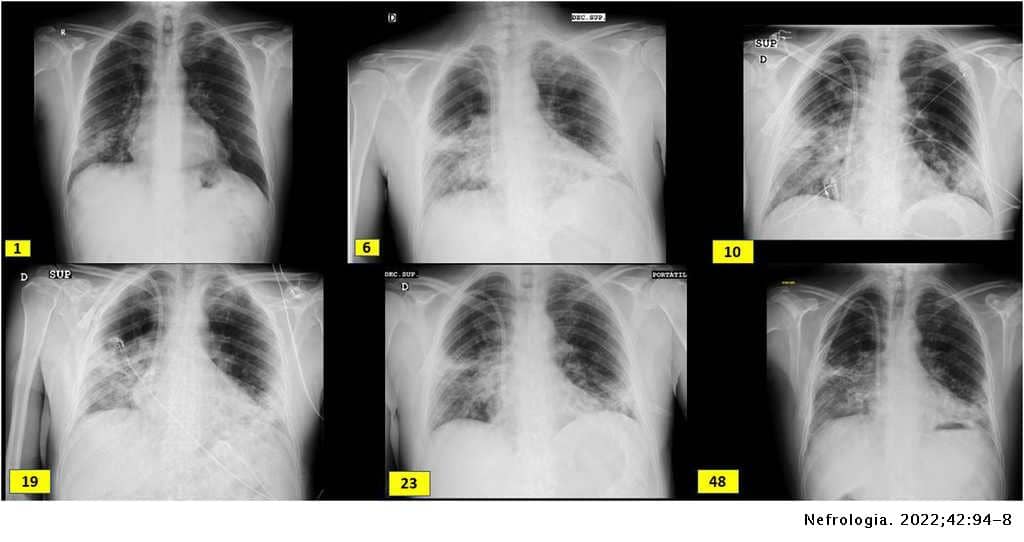

Varón de 60 años de origen ecuatoriano que ingresa en agosto 2020 por disnea de unos días de evolución, sin ningún otro síntoma referido. A su llegada se muestra normotenso y afebril con saturación basal de oxígeno mayor del 94%, pero taquipneico a 16 respiraciones por minuto. Se realiza RT-PCR frente al SARS-CoV-2 en exudado faríngeo con resultado positivo. En el estudio de laboratorio se identifican parámetros habituales de infección COVID, siendo llamativa la afectación renal: Creatinina en plasma 3,94mg/dl, FGe (CKD-EPI): 16, microhematuria e indicios de proteínas (tabla 1). Radiografía de tórax con neumonía bilateral intersticial (imagen 1). El paciente trabajaba como pintor en la construcción, no tenía hábitos tóxicos ni contacto con animales, y era hipertenso de larga duración.

Paralelamente desarrolla hepatopatía parenquimatosa multifactorial (quinolona, hepatotoxicidad vírica y vasculitis hepática) por lo que se sustituye levofloxacino por ceftriaxona. El día 11 sufre anemización sin datos de sangrado renal posbiopsia en la ecografía que precisa hemotransfusión y hemoptisis autolimitada con fibrobroncoscopia sin hallazgos por lo que se administran 3 dosis de 500mg de metilprednisolona. Evoluciona mal, con progresión radiológica de los infiltrados, mayor insuficiencia respiratoria y renal, por lo que el día 16 iniciamos inmunoglobulinas IV a dosis de 0,2mg/kg/día durante 5 días y el día 19, tras recuperar función hepática, tocilizumab, 2 dosis, 600mg el primer día y 400mg el segundo día. Ingresa en la UCI y se trata mediante hemodiafiltración intravenosa continua (HDFVVC) (3 sesiones) y tratamiento respiratorio de soporte con VMNI a alto flujo. De forma lenta mejora renalmente, recupera filtrado glomerular y se estabiliza respiratoriamente con menor débito de oxígeno. Tras comprobar el día 21 serología IgG de COVID positiva, se programa tratamiento con rituximab, 4 dosis de 375mg/m2/semana IV. Se plantea complementar el tratamiento con nueva tanda de inmunoglobulinas, lo que no se lleva a cabo por mantener niveles adecuados en plasma. Estabiliza su función renal con FG 20-30m/min/1,73m2, pero los infiltrados respiratorios y su dependencia ventilatoria no mejoran en las 3 semanas siguientes pese a fisioterapia y soporte adecuado. Por esta tórpida evolución respiratoria se repite la fibrobroncoscopia sin hallazgos relevantes. Finalmente, puede ser dado de alta a los 50 días de ingreso con oxígeno crónico domiciliario y un FGe 27ml/min.